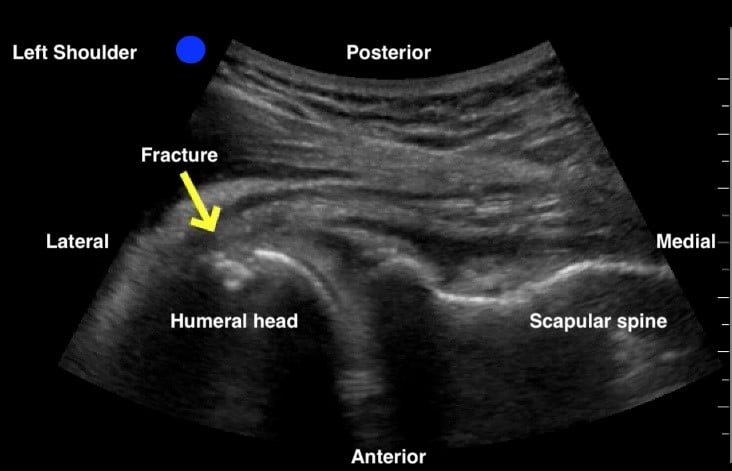

An anterior shoulder dislocation will show the humeral head displaced to the far field region of the screen, while the posterior dislocation will show the humeral head displaced to the near field region (Figures 3 and 4). A shoulder subluxation will show the humeral head partially sliding (or “dislocating”) in and out of the GHJ with shoulder movement (Figure 5). While less accurate, POCUS can also help identify fractures, such as the Hill-Sachs, the Bankart, or a humeral head fracture (Figure 6).

Secko MA, et al. has estimated a 100% sensitivity and specificity in diagnosing a shoulder dislocation by using the posterior approach technique. They also established that an anterior dislocation has a glenohumeral distance cutoff value of at least 0.5 cm.6

Figure 4: Non dislocated left humeral head fracture. Humeral head and neck fracture confirmed on plain x-ray